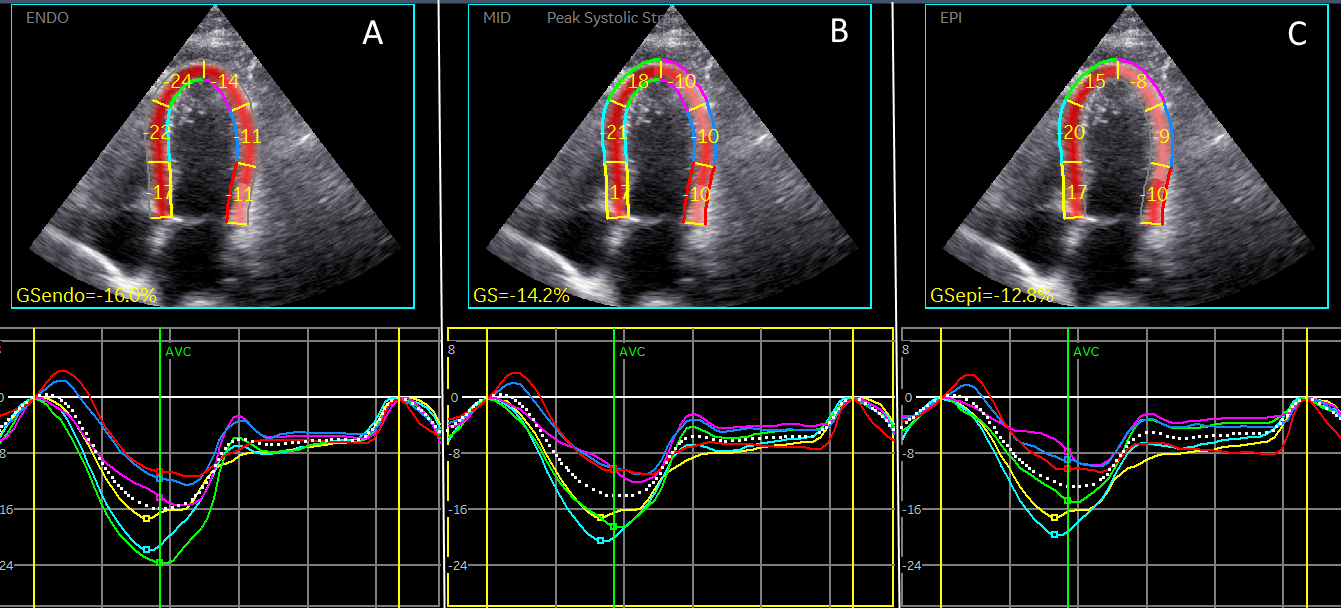

We evaluated GLS that is transmural strain. Myocardial wall is composed of 3 myocardial layers, endocardium, epicardium and mid-layer and strain can be calculated in each of them [1], that may provide further insights into post-COVID complications. Which layer is responsible for decrease of GLS in post-COVID patients? In which myocardial layer myocytes are more vulnerable regarding the binding by viral particles? As we can see at Figure 1, endocardial strain is the highest and the epicardial strain is the lowest.

Figure 1. Strain in 3 myocardial layers in patient with post-COVID syndrome. Apical 4-chamber view.

1. Endocardial strain.

2. Mid-layer strain

3. Epicardial strain.

Myocardial involvement in inflammatory myocardial diseases usually epicardial and mid-myocardial and strain is decreased at basal and mid-ventricular segments [2]. In coronary artery disease endocardial layer is damaged first. What can we anticipate discovering in post-COVID patients who do not exhibit clinical signs of myocarditis or myocardial infarction? One area of interest is left atrial strain. Left atrial function is crucial for optimal cardiac performance, and strain analysis provides valuable insights into its contractile properties. Recent studies have shown that patients with post-COVID complications tend to have reduced left atrial strain compared to healthy individuals [3]. This reduction of strain suggests a potential impairment in left atrial function, which can have important implications for patients' overall cardiovascular health. Tropism of SARS-CoV-2 virus was found in the cardiomyocytes of the left atrium [4]. in this study we didn’t analyzed left atrial strain that can also help to elucidate the kind of cardiac dysfunction in patients with post COVID syndrome, Figure 2.